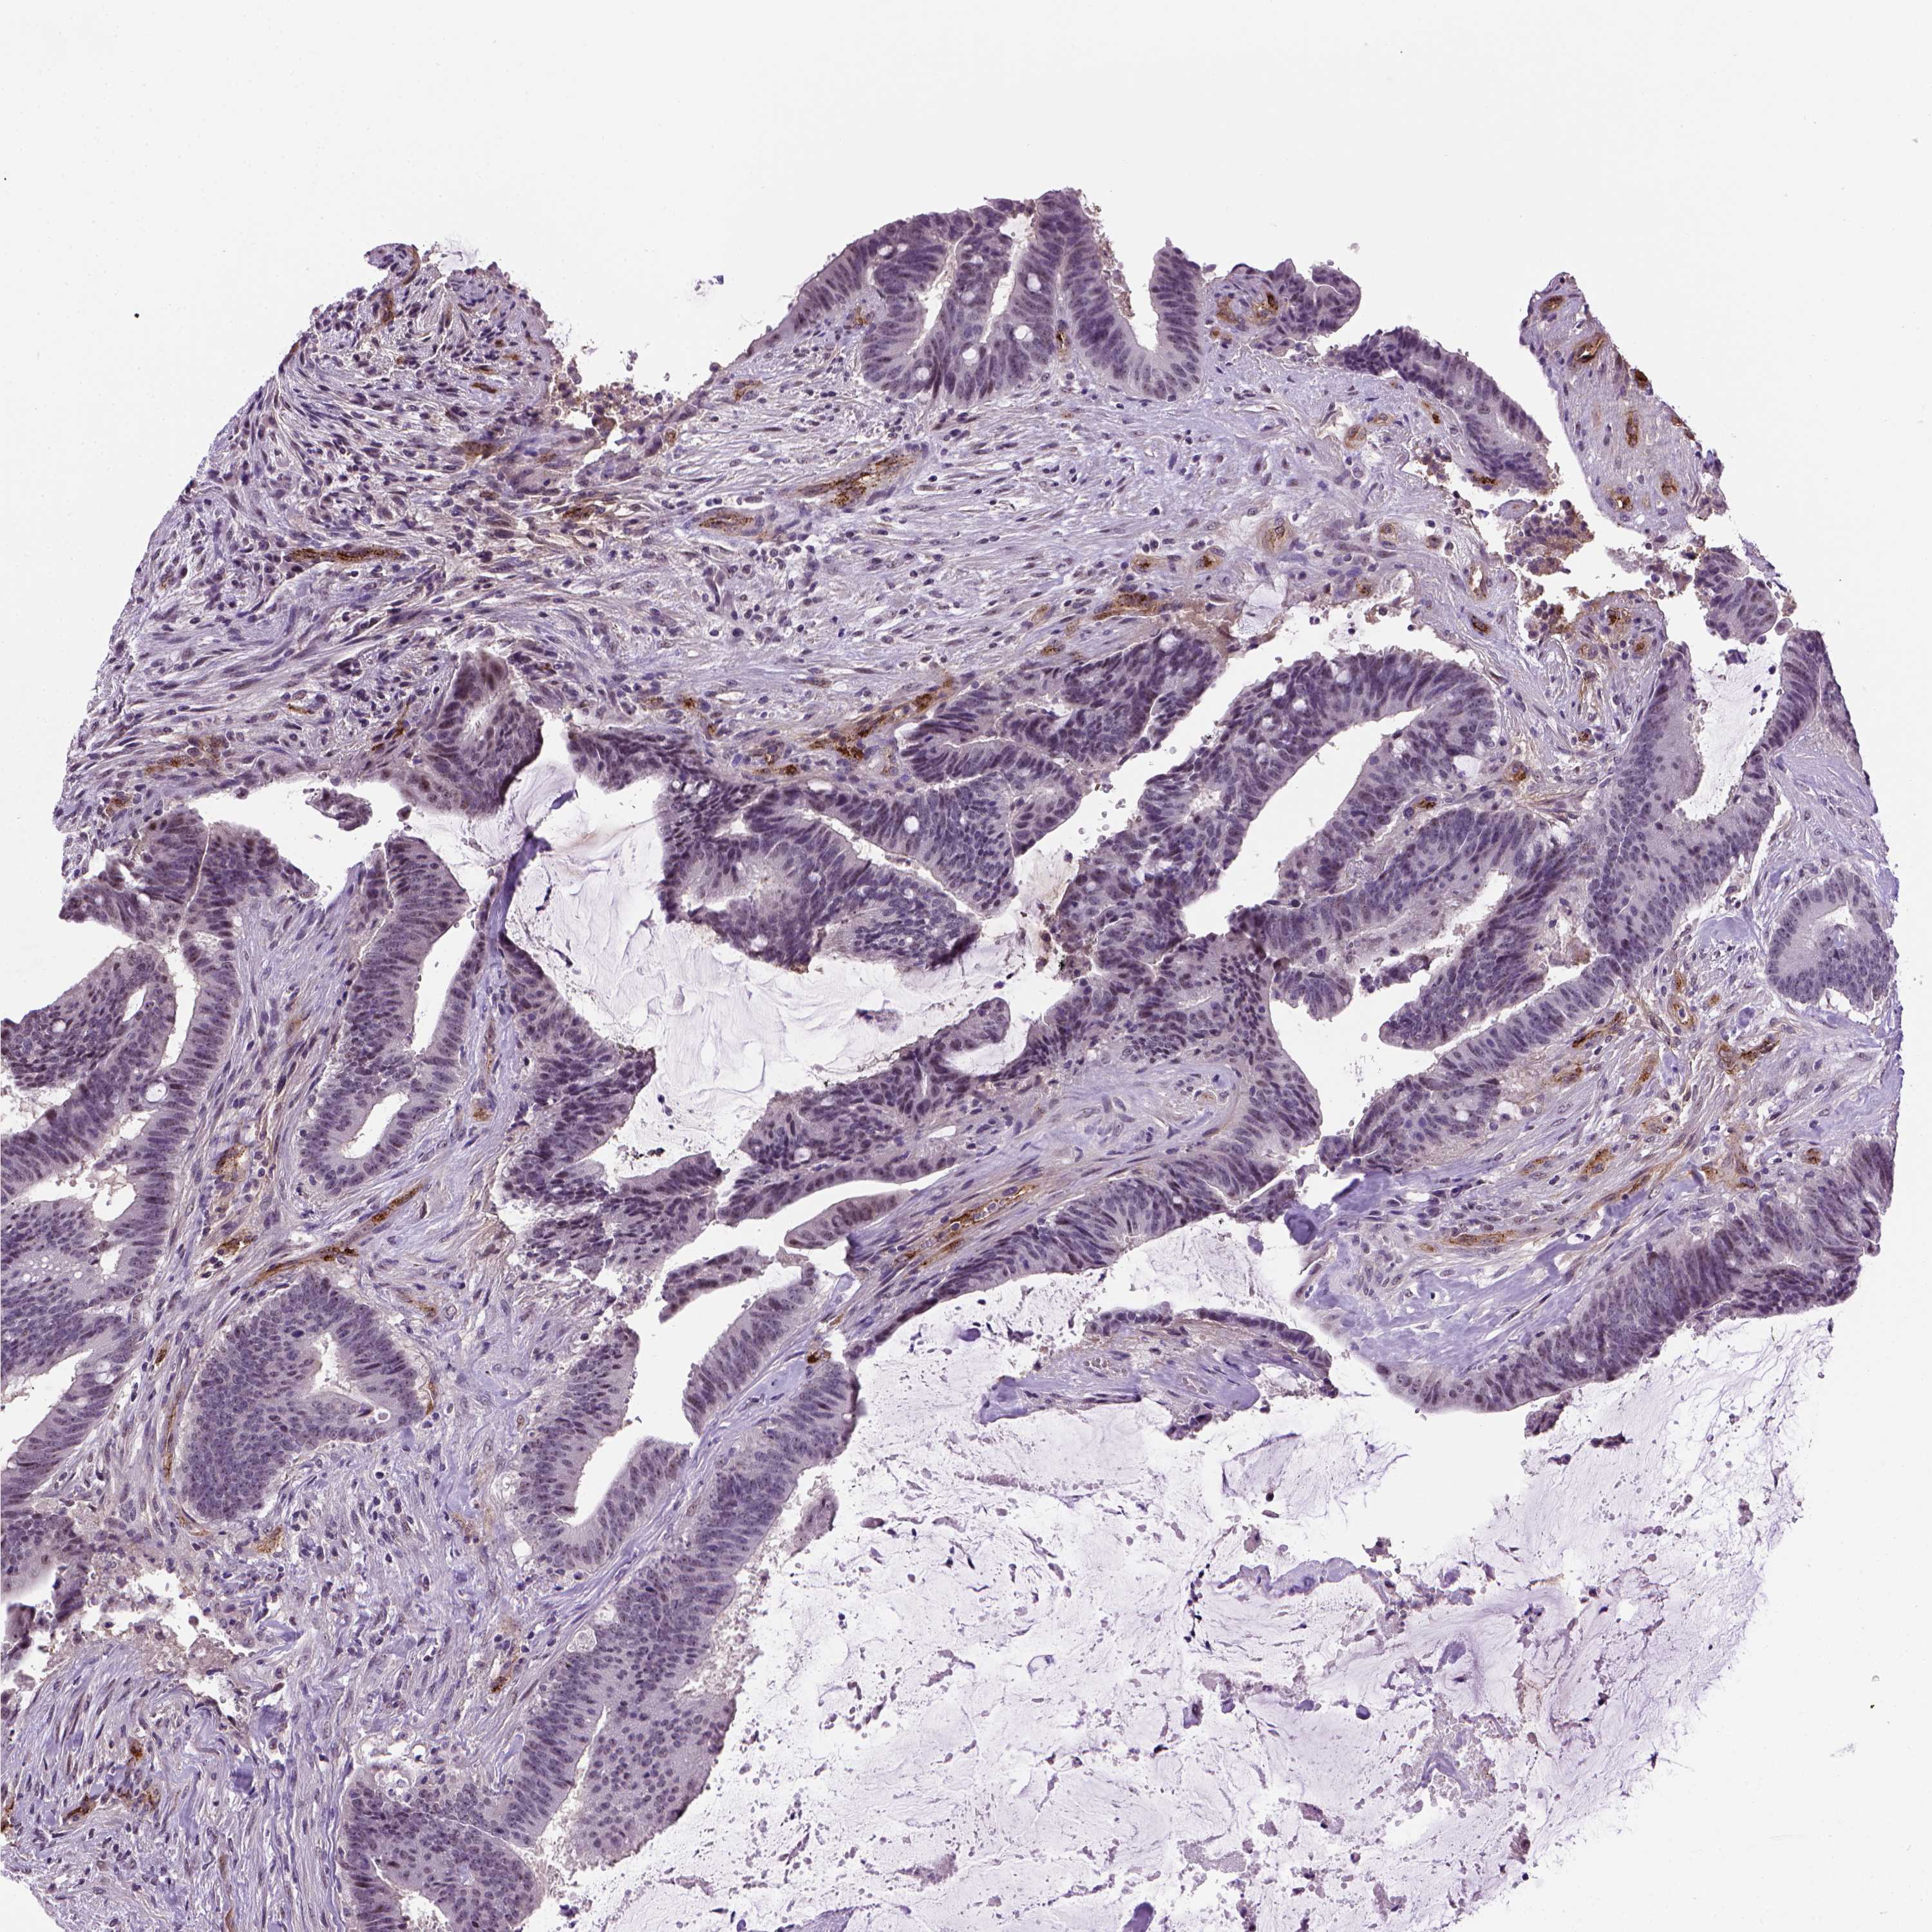

CANCER COLORECTAL CANCER Show tissue menu

ANTIBODIES

AND

VALIDATION